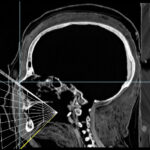

Cross-sectional images

A stack of transverse cross-sectional images from computed tomography (CT, left) forms the basic material for the Virtual Mummy. Various structures such as the light bone and the somewhat darker linen wrapping surrounding it are clearly visible. The sagittal (center) and coronal (right) sections are reconstructed from this.